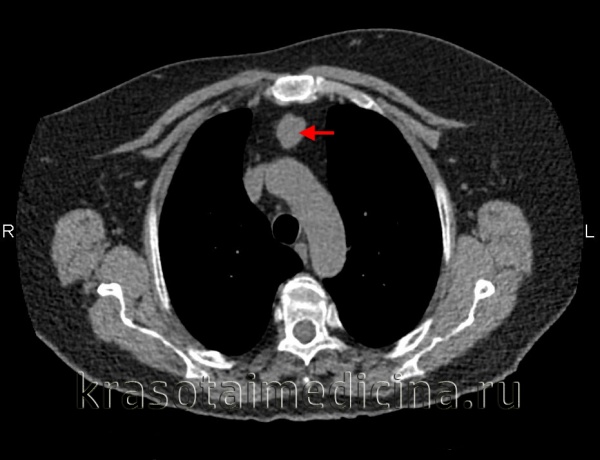

Компрессионный синдром

Компрессия венозных стволов, прежде всего, проявляется так называемым синдромом верхней полой вены (СВПВ), при котором нарушается отток венозной крови от головы и верхней половины туловища. Синдром ВПВ характеризуется тяжестью и шумом в голове, головной болью, болями в груди, одышкой, синюшностью и отечностью лица и грудной клетки, набуханием вен шеи, повышением центрального венозного давления. В случае сдавления трахеи и бронхов возникают кашель, одышка, стридорозное дыхание; возвратного гортанного нерва - дисфония; пищевода – дисфагия.